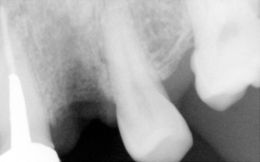

Terminato l’intervento chirurgico implantare, è stata effettuata una radiografia endorale (rx rvg ) di controllo, in cui emerge un sottile spazio di uno trasparente peri-implantare e di materiale riempitivo Sint Life Putty (MHA);